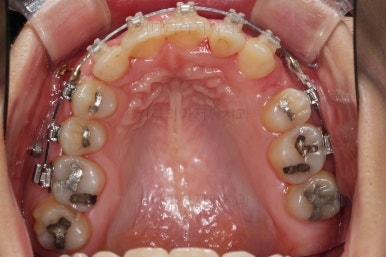

장치를 구성합니다.

이번 환자분은 윗니는 세라믹, 아랫니는 메탈 장치를 선택하셨는데요.

둘 다 물론 자가결찰 장치였고요.

동일한 제품의 장치이므로 혼용해서 쓰는게 가능합니다.

많이 보이는 부분은 세라믹, 잘 안보인다고 여겨지시는 부분은 메탈로 선택하면서 치료비 측면도 함께 고려한거죠.

아랫니는 발치 없이 가지런하게 해주고요.

윗니는 가지런하게 한 뒤 발치공간을 서서히 닫아줍니다.

유치는 크기가 작았기 때문에 생각보다 빨리 공간이 닫히고 있고요.

반대쪽 작은 어금니 부분은 공간이 아직 많이 남은 편이죠.

매복치아 발치 부위의 앞니도 이미 뿌리가 약간 손상된 상태였기 때문에 교정 중에도 경과 관찰을 잘 해줘야 합니다.